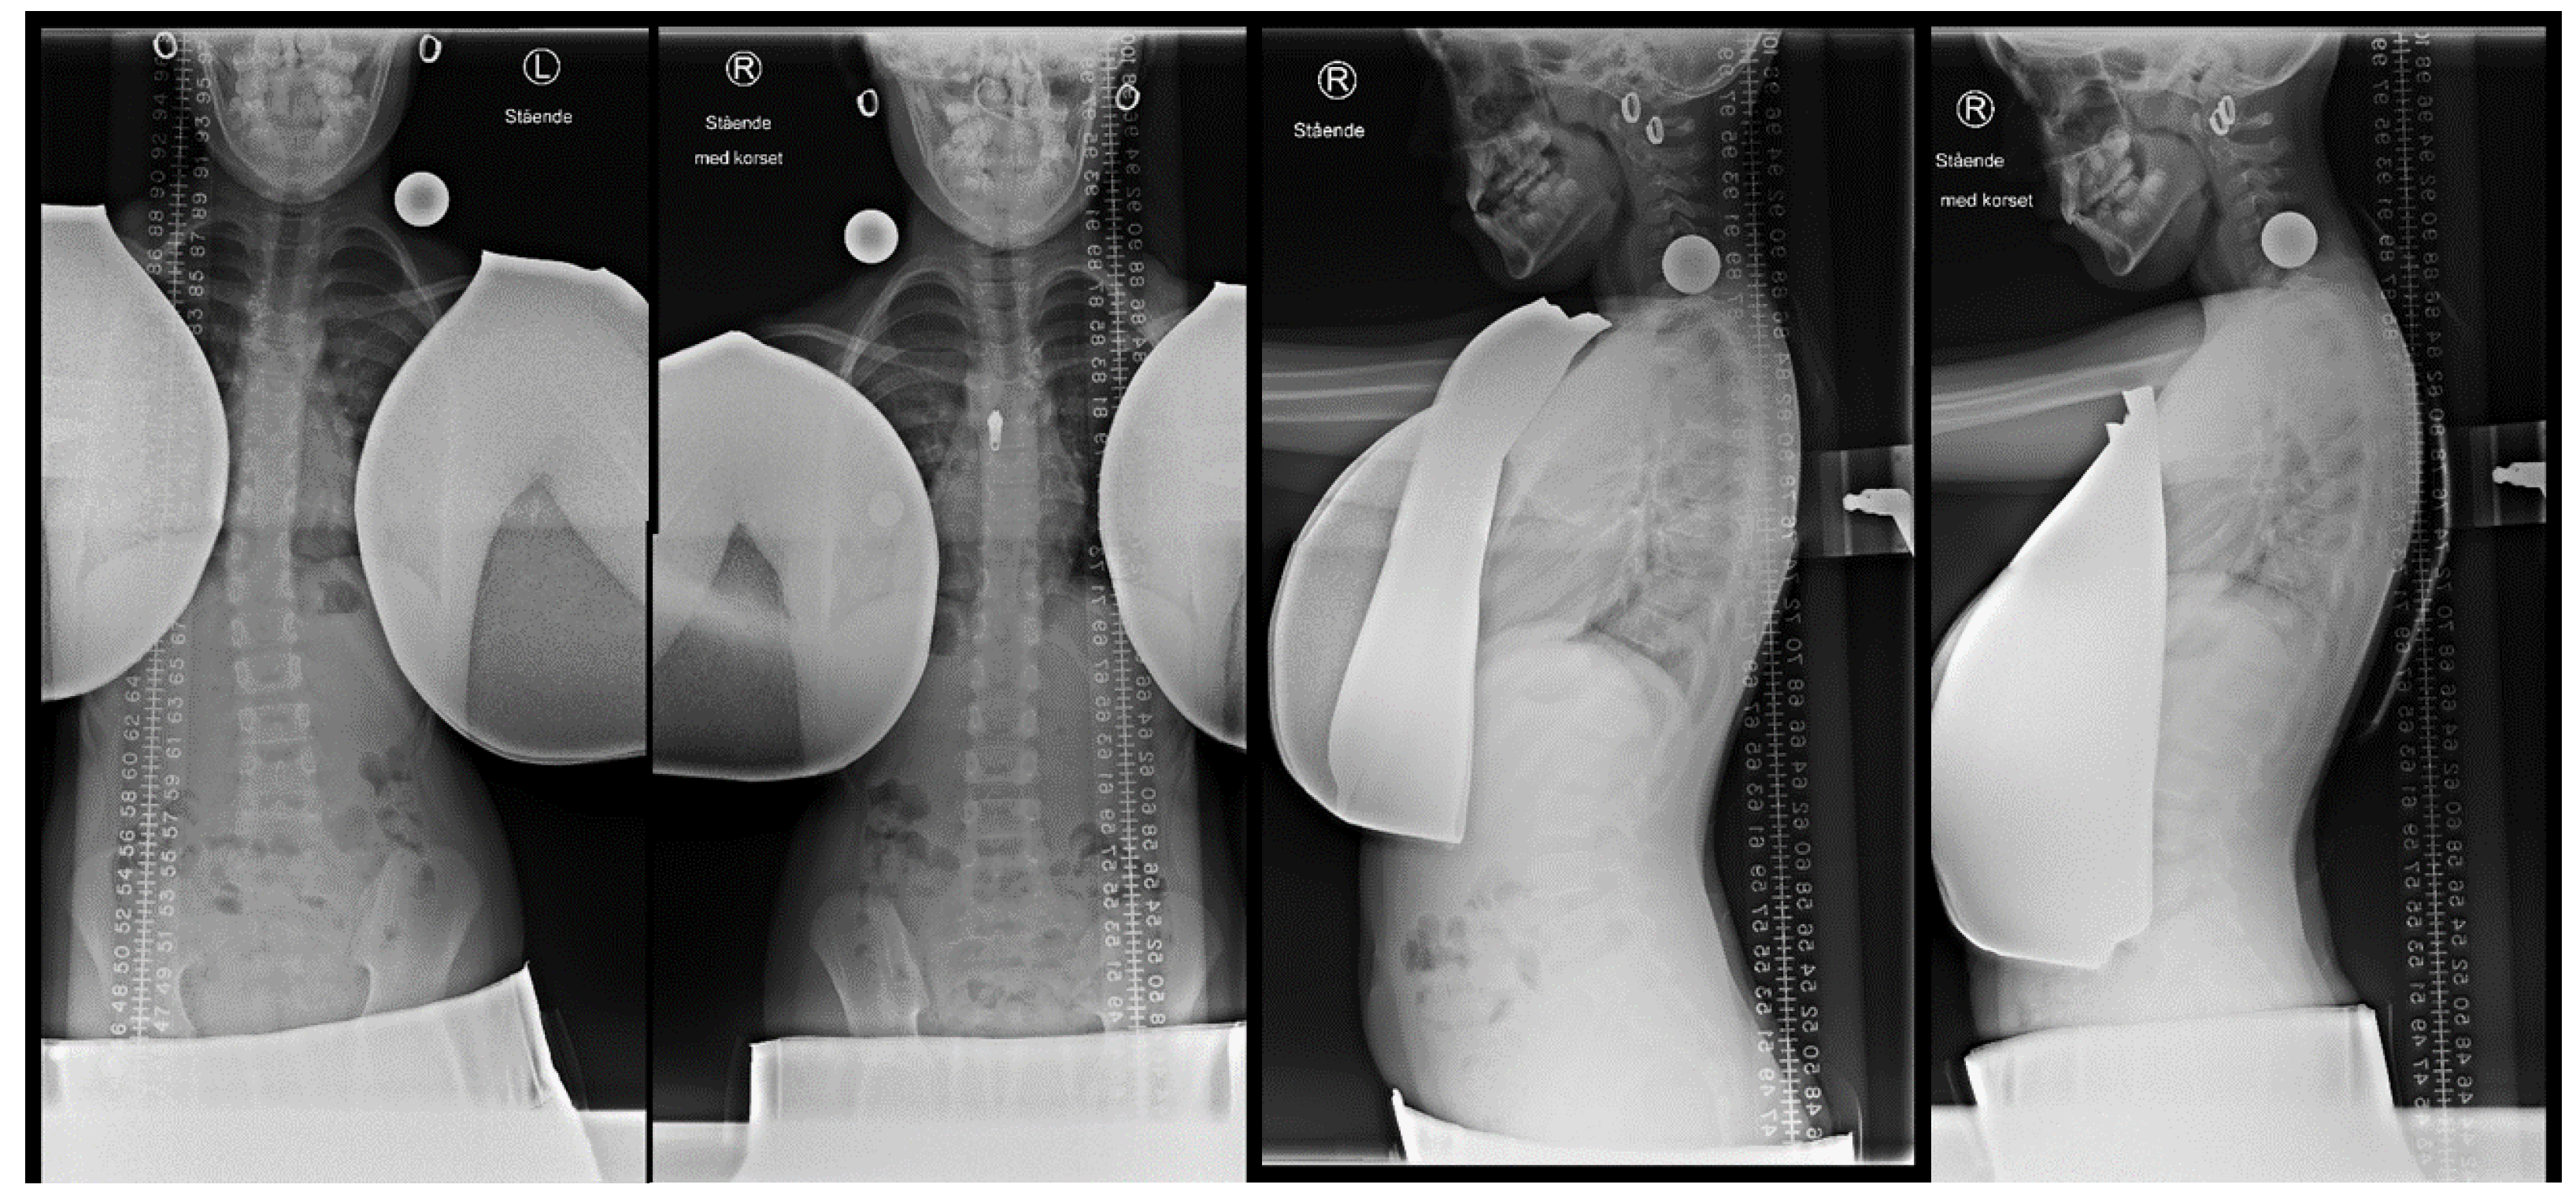

2.2. Initial in-Brace Radiographs

3.2. In-Brace Correction